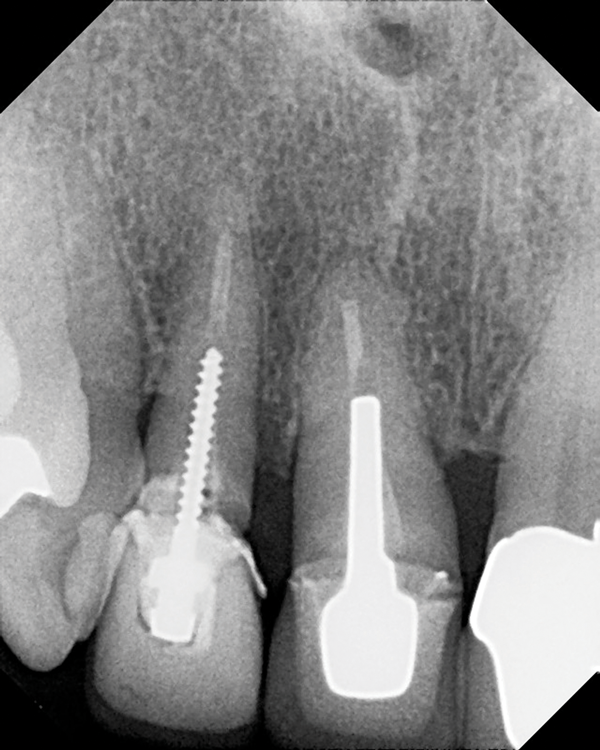

(3.) Radiograph of a loose screw-style metal post.

Figure 3